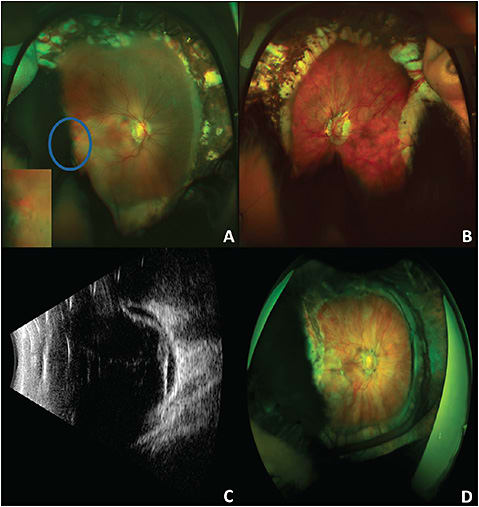

A 19-year-old woman presented with decreased vision in the right eye for 2 weeks. Her past medical history included prematurity and developmental delay. She also developed ROP, which was treated with laser photocoagulation. Visual acuity (VA) was “counting fingers” in the right eye and 20/200 in the left eye. There was horizontal nystagmus in both eyes. An anterior slit lamp exam was normal. Posterior examination showed a myopic appearing disc with peripapillary atrophy, shallow subretinal fluid within the macula and a near peripheral retinal detachment extending to a peripheral zone of 360° laser photocoagulation (Figure 1A). Examination of the fellow eye showed a myopic-appearing fundus with peripheral laser scars and no detachment (Figure 1B). An ultrasound was also performed, which showed a total retinal detachment with the temporal break previously visualized along with another break at 12 o’clock (Figure 1C). The patient underwent repair with combined pars plana vitrectomy (PPV) with scleral buckling, drainage through the preexisting break, air fluid exchange, endolaser, and instillation of 1,000 centistoke silicone oil. At postoperative month 6, the patient’s VA was “E” at 4 feet, and silicone oil removal was discussed with the family and patient, but they elected to observe (Figure 1D).